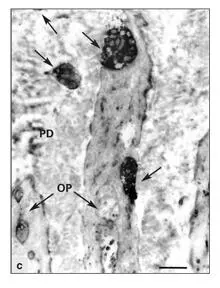

Because the cell processes of fibroblasts and odontoblasts can be confused with unmyelinated nerve fibers, special staining techniques are needed to accurately distinguish nerve fibers and their terminals. Protein gene product 9.5, a neuron-specific protein, has been used to identify pulpal nerve fibers at both the light and electron microscopic level (see Figs 2-10ato 2-10d). 140 , 144Fibers containing protein gene product were present in both radicular and coronal predentin. Nerve endings in the predentin have also been identified by immunocytochemistry for calbindin, a calcium-binding protein found in high concentrations in nerve cells. 145Tracer experiments with tritiated proline injected into the brainstem nuclei of the trigeminal nerve have provided convincing proof of a rich supply of sensory nerve terminals in the predentin and dentinal tubules. 146

Figs 2-10a to 2-10dNerve structure of a human premolar. (Human protein gene product [PGP] 9.5 antibody stain. Adapted from Maeda et al 140with permission from Elsevier Science.)

Fig 2-10cElectron immunocytochemistry. Nerve terminals (arrows) stained with PGP 9.5 antibody are juxtaposed to the odontoblastic processes (OP) in the predentin (PD). (Original magnification × 4,000.)